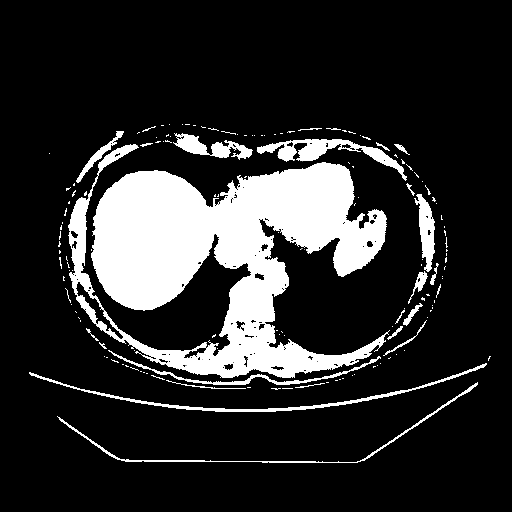

Generated VENOUS CT scan (A→B translation)

Full window (WL 1023.5, WW 4095 β†’ Low βˆ’1024, High +3071)

Actual HU range: [-1024.0, 3071.0]